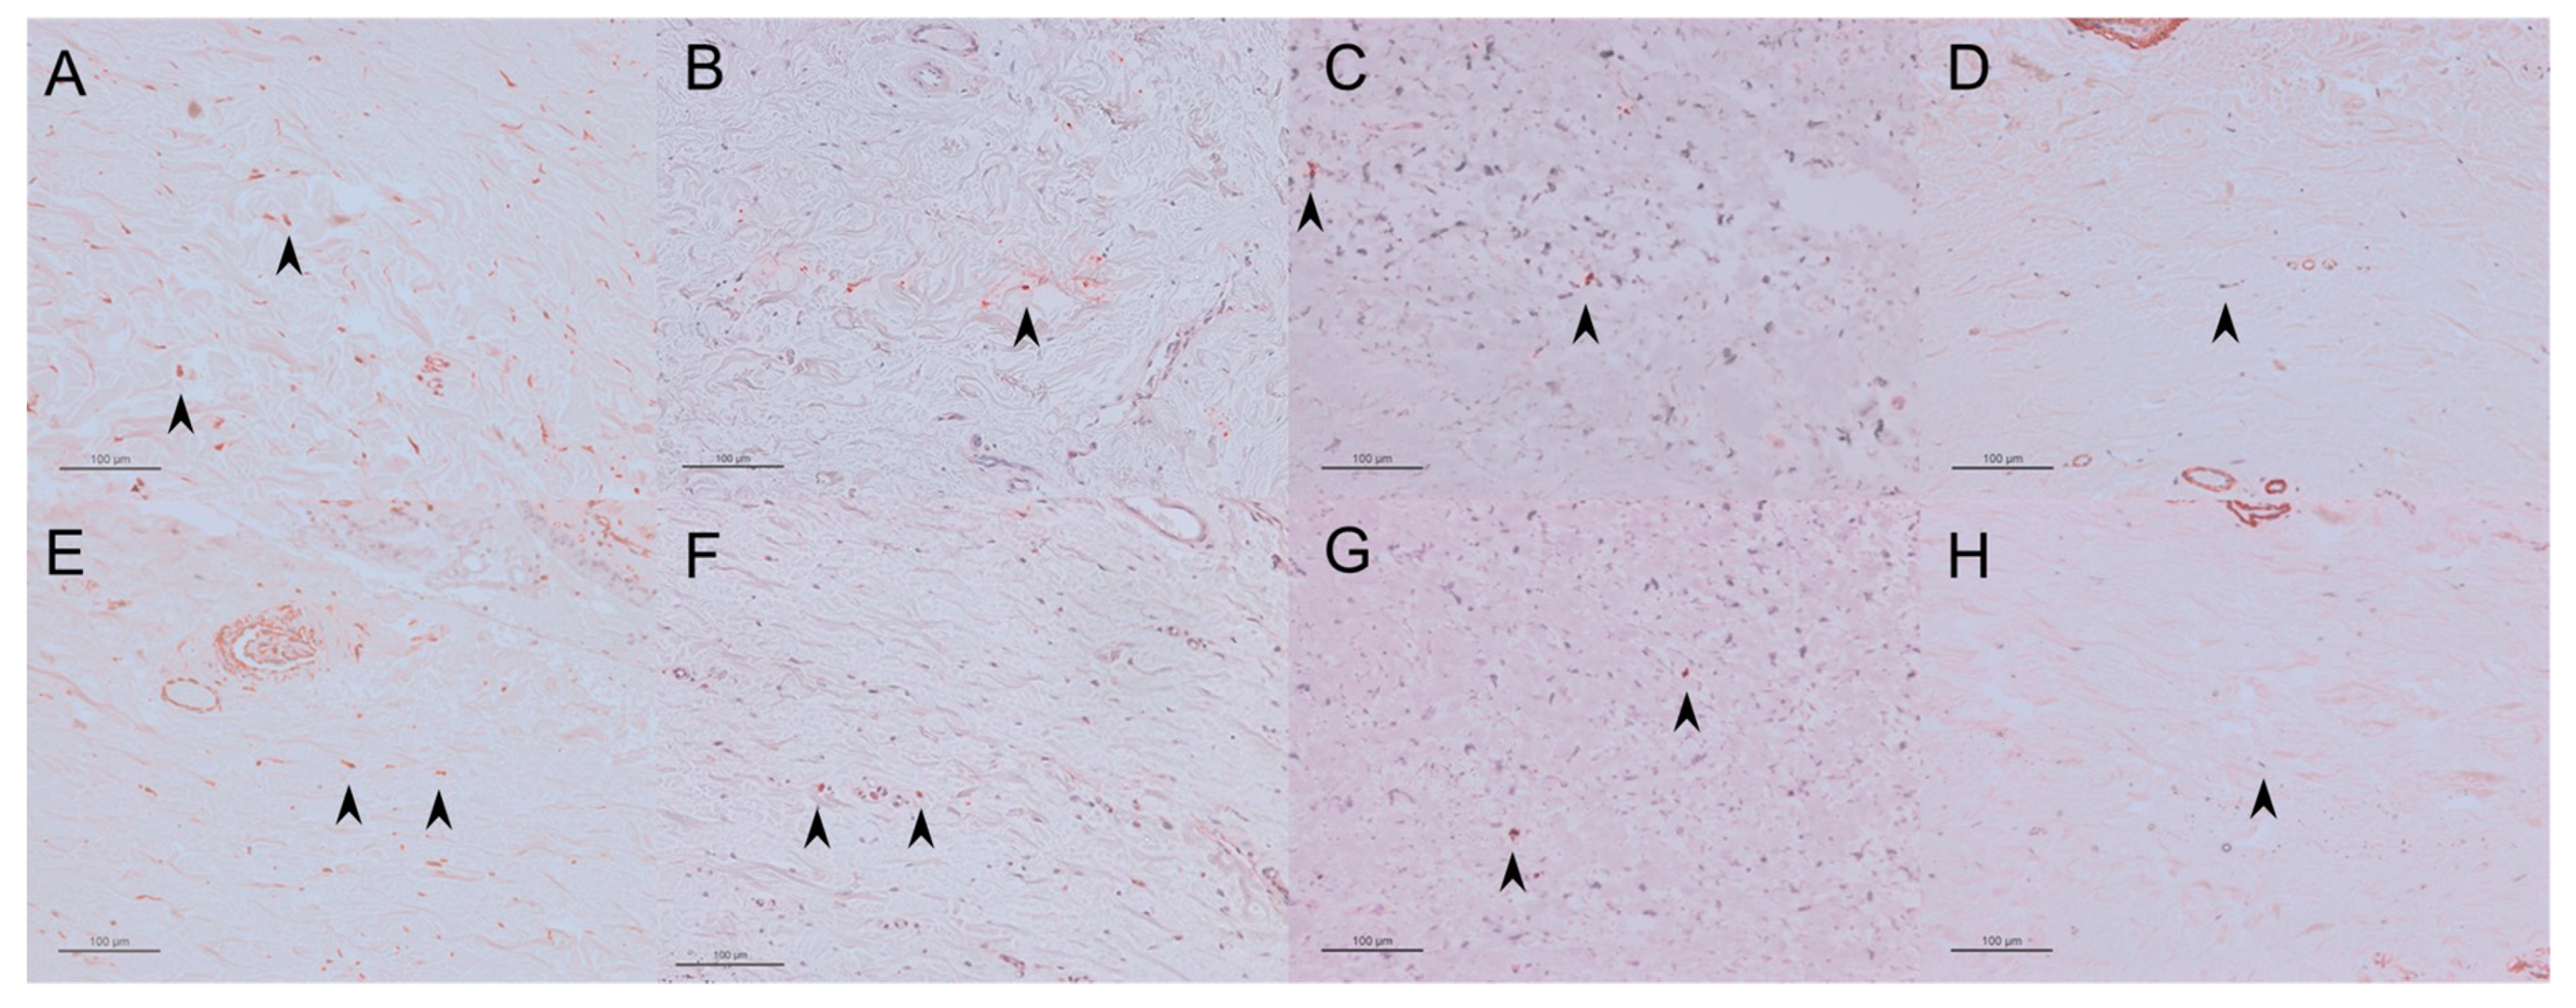

2.1.6. Vimentin-, TGF-β-, Proliferative Cell Nuclear Antigen (PCNA)-, and αSMA-Positive Cells

2.2.6. Vimentin-, TGF-β-, PCNA-, and SMA-Positive Cells